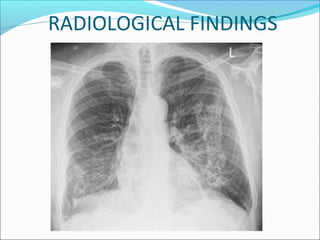

RADIOLOGICAL FINDINGS

There are typically rounded

opacities of varying sizes in upper

zones. These opacities can be

round or irregular in outline.

They may calcify and coalesce into

large masses in PMF